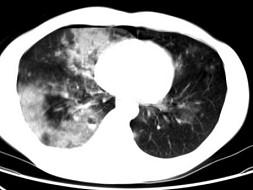

男,28岁,外伤后1小时行胸部CT如图,其最可能的诊断为 ( )A、肺癌B、双肺挫伤C、肺脓肿D、肺囊肿E、肺炎

问题 男,28岁,外伤后1小时行胸部CT如图,其最可能的诊断为 ( )

选项 A、肺癌 B、双肺挫伤 C、肺脓肿 D、肺囊肿 E、肺炎

答案 B